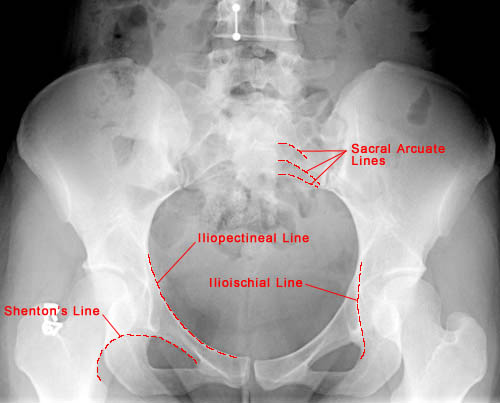

AP view showing important anatomical lines of the pelvis